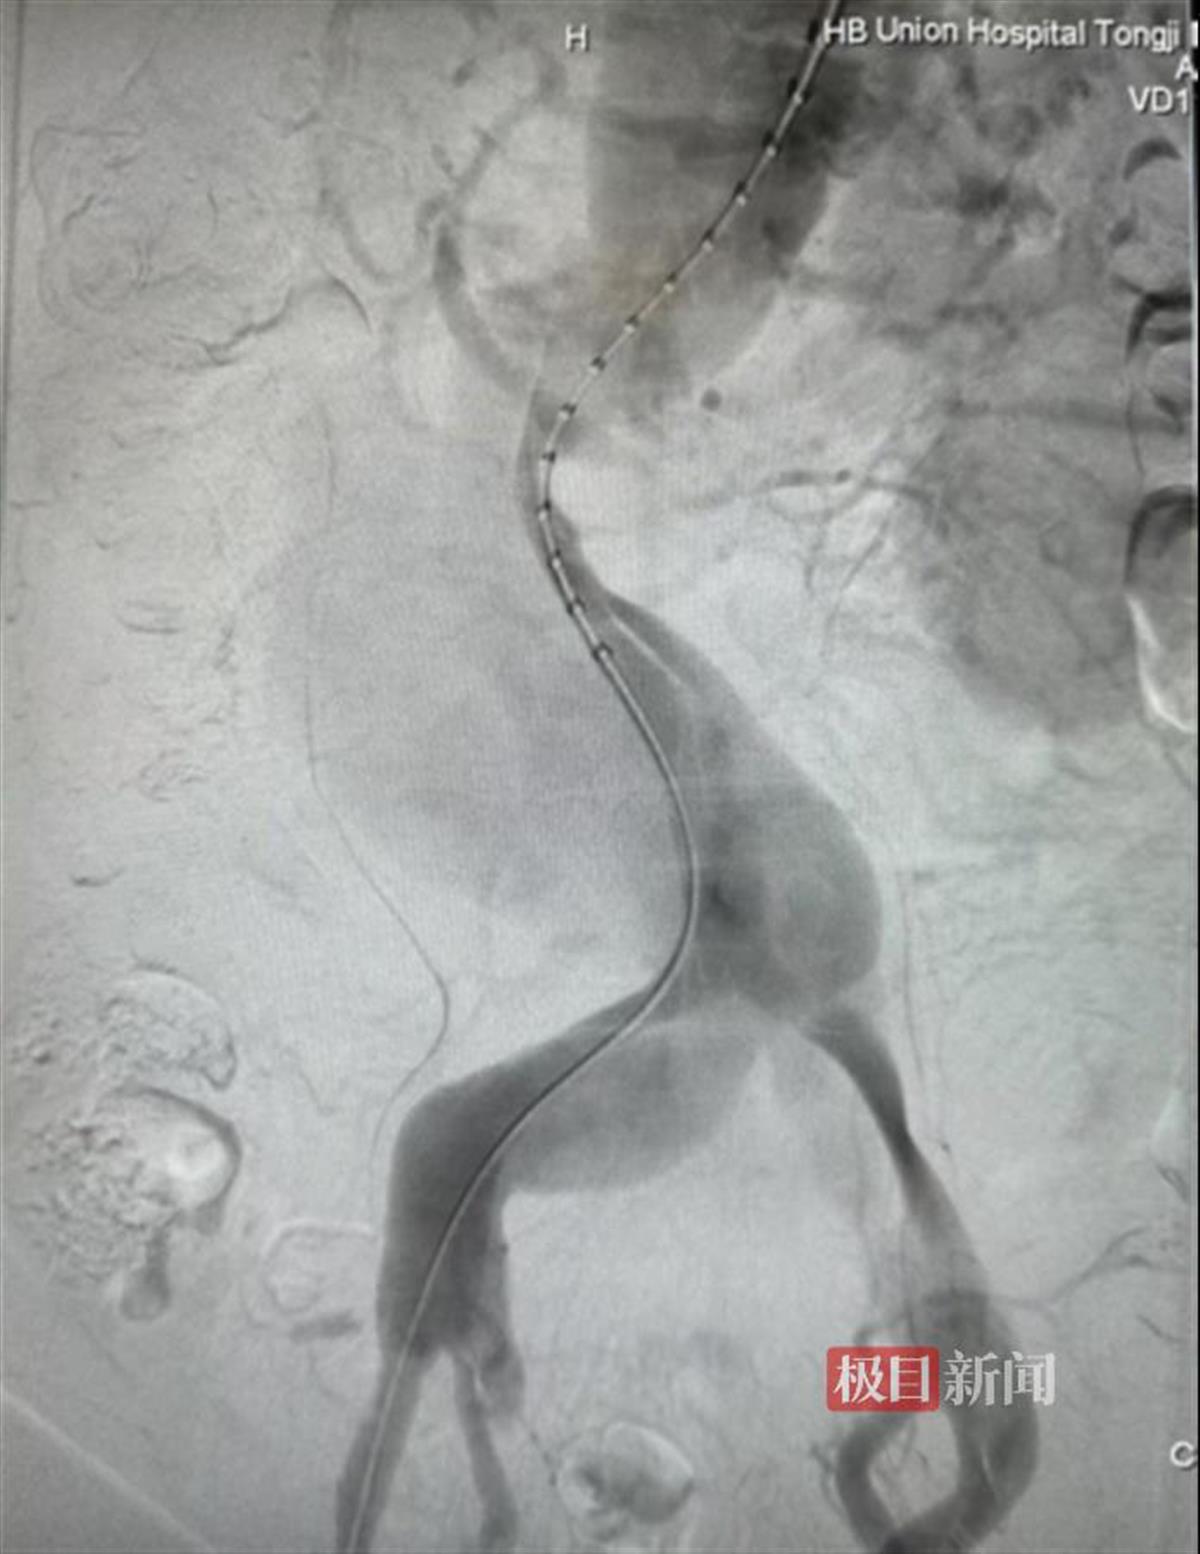

支架置入前造影见巨大胸腹主动脉夹层动脉瘤

手术包括体外改装支架和腔内支架置入两大环节。首先需要在体外将支架改装,即在主动脉支架上按照术前测量的数据进行开窗,部分分支需要在“窗口”上缝合内嵌或外嵌分支,再将改装好的主动脉支架重新收回输送器。根据术前计划建立好通路,将改装好的支架送入患者体内后,再经支架内分别选入预开的四个窗口,并进入患者的分支动脉,并接入桥接支架来保证上述分支动脉的正常血流。经过5小时的手术,终于按照预期隔绝了破裂的腹主动脉夹层动脉瘤,同时各分支动脉血流通畅,保证了重要脏器的血供,手术效果非常理想。